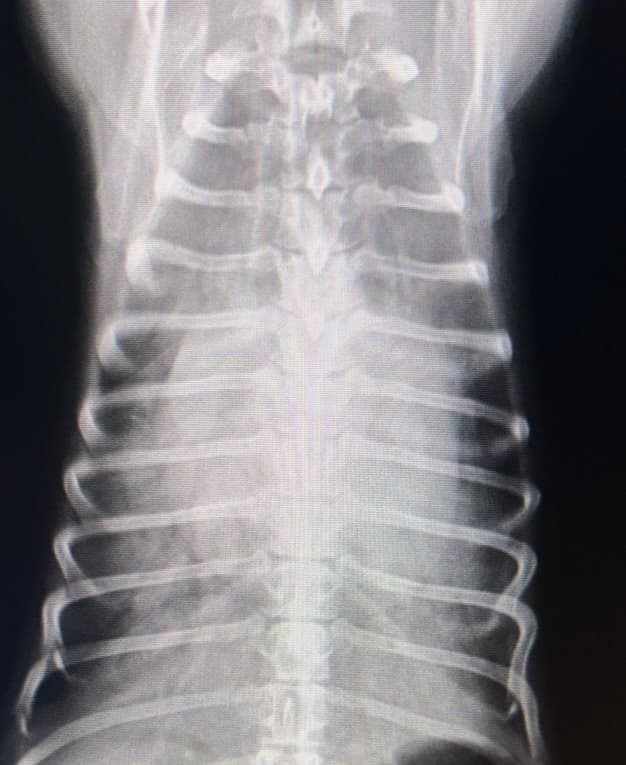

動脈管開存症(2025/09/09)

動脈管開存症とは犬の先天性心疾患で最も多いとされる病気です。産まれる前の胎児期にはたらいていた、大動脈と肺動脈をつなぐ動脈管という血管が遺残してしまうことで全身に行くはずの血液が肺動脈へと流れ、肺静脈や肺に過剰な負担がかかります。聴診で特徴的な雑音が聴取され病気が見つかることもありますが、確定診断にはエコー検査を用います。初期は無症状のこともありますが、重症化すると、疲れやすい、咳をする、呼吸が苦しいなどの症状が見られます。自然に血管が塞がることもありますが、症状が強い場合は手術で血管を塞ぐ必要があります。子犬に気になる症状がある場合は、ご相談ください。